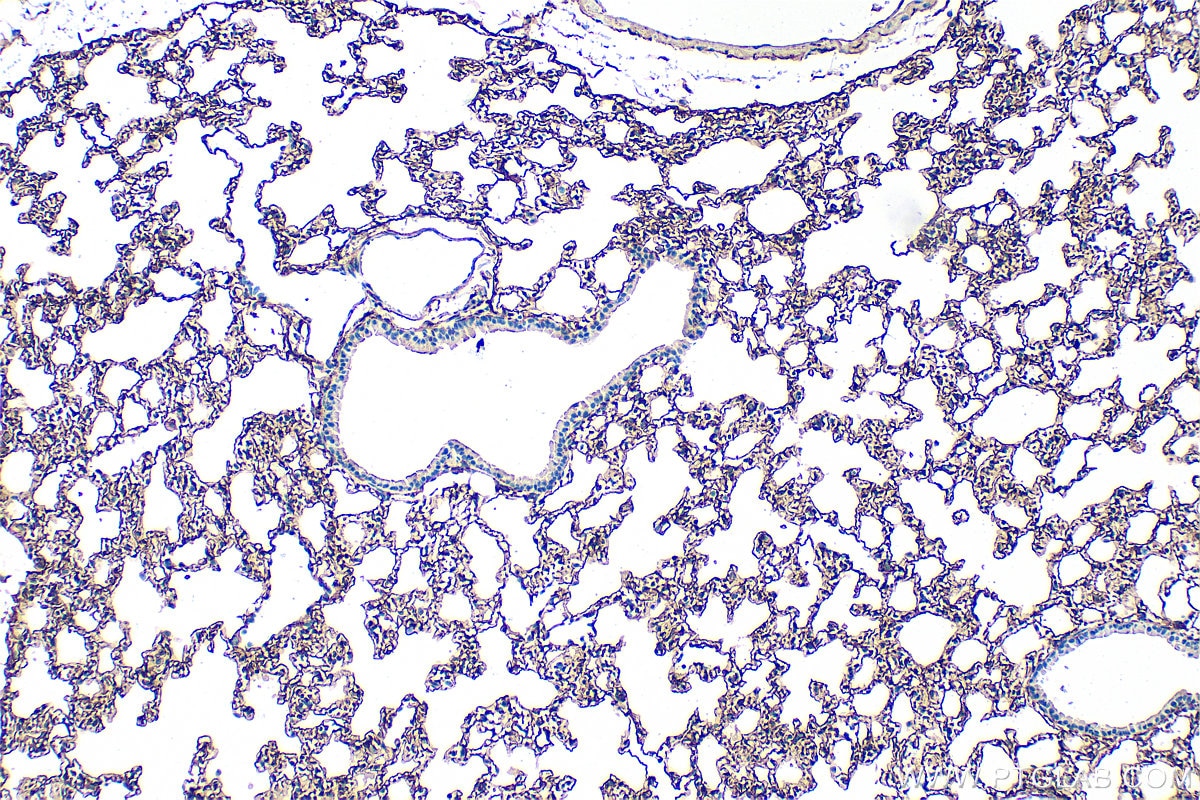

| Positive IHC detected in | mouse lung tissue, mouse kidney tissue Note: suggested antigen retrieval with TE buffer pH 9.0; (*) Alternatively, antigen retrieval may be performed with citrate buffer pH 6.0 |

33099-1-AP targets Podoplanin in WB, IHC, ELISA applications and shows reactivity with mouse samples.

Podoplanin was identified as a glycoprotein found in the cell membranes of glomerular epithelial cells (podocyte) (PMID: 9327748). It is a lymphatic marker because the expression of podoplanin has been detected in lymphatic but not blood vascular endothelium, and is useful as the marker of tumor-associated Lymphangiogenesis. Podoplanin has a function in developing testis, most likely at the level of cell-cell interactions among pre-meiotic germ cells and immature Sertoli cells. It may be involved in cell migration and/or actin cytoskeleton organization. When expressed in keratinocytes, PDPN induces changes in cell morphology with transfected cells showing an elongated shape, numerous membrane protrusions, major reorganization of the actin cytoskeleton, increased motility and decreased cell adhesion. It is required for normal lung cell proliferation and alveolus formation at birth. PDPN induces platelet aggregation. It does not have any effect on folic acid or amino acid transport and does not function as a water channel or as a regulator of aquaporin-type water channels.